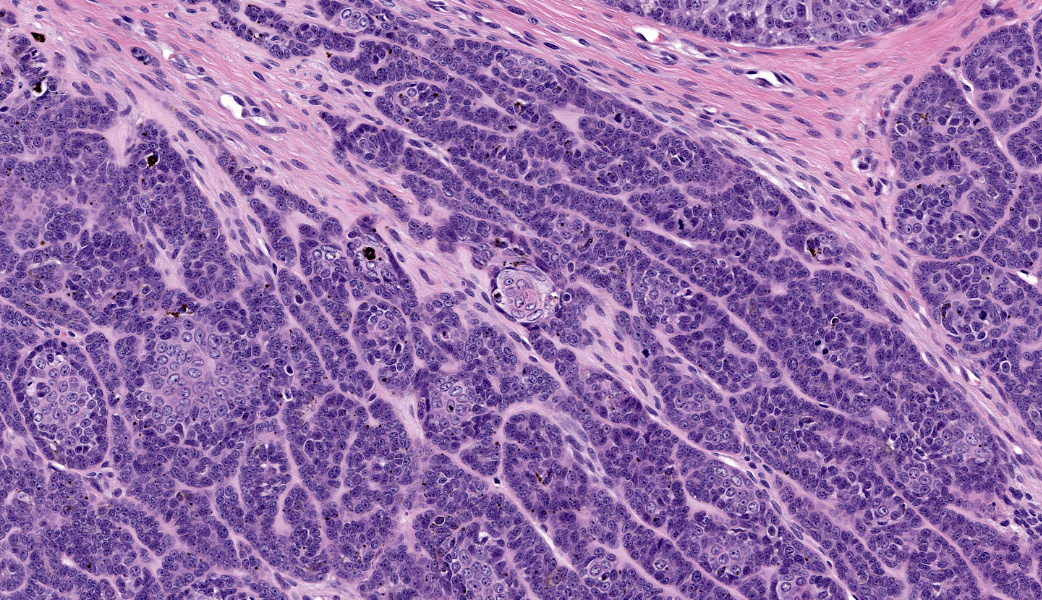

Haired skin: Extending from the dermis deep into the subcutis is an approximately 2 x 2 cm well-demarcated cystic mass lined by neoplastic undifferentiated basaloid epithelial cells. The neoplastic cells are arranged in lobules of dense anastomosing and palisading cords or small tightly packed nests, supported by scant fibrovascular stroma. There are multifocal papillary projections of neoplastic lobules into the lumen of the large cystic cavity. Multifocai lobules have smaller central cyst formation. The neoplastic basaloid cells are cuboidal with scant basophilic cytoplasm and round to oval, hyperchromatic nuclei, with two or more prominent nucleoli. There is minimal anisocytosis and moderate anisokaryosis. There is multifocal abrupt squamous differentiation and necrosis and approximately 5 mitotic figures per high power field. Brown granular pigment, most consistent with melanin, is present throughout the periphery of the mass; multifocal melanomacrophages infiltrate neoplastic lobules. Neoplastic cells extend to within 2 mm of the surgical margin; however, there are multifocal foci suspicious for local invasion.Contributor's Morphologic Diagnoses:

Histologically, basosquamous carcinomas are predominately composed of intradermal to subcutaneous lobules of undifferentiated basal cells with central foci of abrupt squamous differentiation.1 Keratinocytes at the center of neoplastic lobules have mild “nuclear pleomorphism, mitotic activity and dyskeratosis.”1 Unlike other epidermal neoplasms, connection to the overlying epidermis is not a consistent diagnostic feature.4 However, cyst formation and melanization, as seen in this case, are common and can often be appreciated grossly.1,4 Keratinocytes, present in the foci of abrupt and atypical keratinization, that display features of malignancy, along with “the lack differentiation of the follicular isthmus or bulb are features that help differentiate basosquamous carcinomas” from other tumors.4

In human literature, it is currently believed that the BSC initially arises as a BCC that then undergoes genetic and epigenetic alterations, ultimately leading to squamous differentiation through basal-to-squamous transition (BST). As such, the BSC was classified as a BCC variant by the WHO in 2023.7 To further complicate matters, there are also “basaloid SCC” and “keratotic BCC” diagnoses in humans, as well as BCC/SCC collision tumors.7 Participants were shown histologic images of what the moderator currently uses to differentiate between a keratinizing BCC, a basaloid SCC, and a BSC. The basaloid SCC is typically described as having comedonecrosis with squamous differentiation at the edges of lobules and is NOT classified as a skin tumor. Rather, it is found in the oral cavity, cervix, lung, etc.7 The keratotic BCC variant is composed of horn cysts, parakeratotic cells, and abrupt keratinization.7 BSC is identified by abrupt squamous differentiation (not abrupt keratinization) with dyskeratotic squamous cells within the center of lobules of basal cells.7 Both the basal cells and keratinocytes have mitotic activity. Considering these factors, a diagnosis of BSC was favored by participants. Ultimately, though, there seems to be substantial disagreement on how to define the BSC in veterinary literature, even between prominent tumor texts and fascicles.